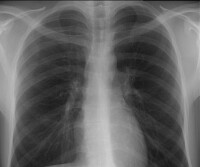

Røntgenbilde av en frisk lunge

Lunge uten silikose

Røntgenbilde av en lunge med silikose

Lunge med silikose